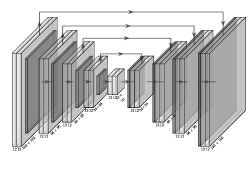

For this purpose we propose a new network structure, similar to FlowNetSimple [36], general enough to produce global motion estimations but parameterized only by few parameters to prevent the network from overfitting. This U-net [47] like structure with depth and a depth-independent number of channels , here and in the following denoted by V-net, is visualized in Figure 1. The depth is chosen according to where is the discrete resolution of the image. The activation is chosen as leaky-ReLU with negative slope coefficient .